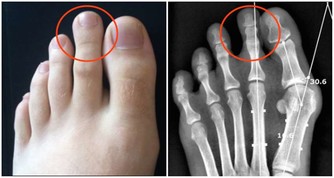

腳通全身搓腳健腦、防百病

眾所周知,腳底分佈著人體全身的反射區。經常搓腳心,對高血壓、神經衰弱、各類頭暈頭痛、耳鳴、失眠、腸胃疾病都有特別好的輔助治療作用,還能健腦。

方法:用左手掌搓右腳心,用右手掌搓左腳心,每隻腳搓100次左右,最好搓到腳心發紅發熱,如能配合熱水泡腳更好。